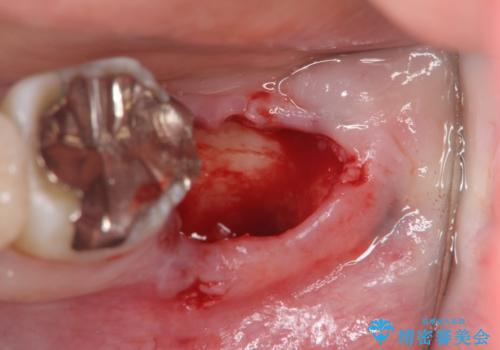

今後の機能回復方法としてインプラント治療を希望されたため、将来的に大規模な骨造成が必要とならないよう歯槽堤保存術を抜歯と同時に行いました。

良好なインプラントの植立を行うためには、十分な骨量があることが必須条件です。

術前、歯の破折により大きな骨の吸収が認められていたため骨量を十分に回復するために抜歯と同時に歯槽堤保存術を行い十分な骨量の回復をすることができました。